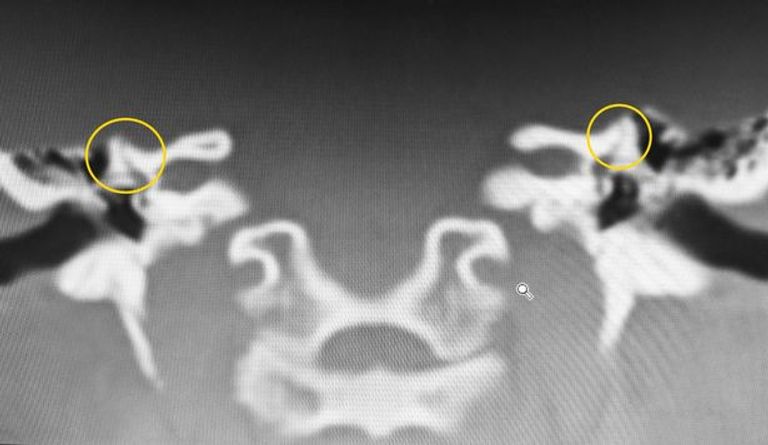

Gemäß den Berichten hatte Gemma einen medizinischen Zustand ‚Bilaterale Superior-Halbkreisförmige Dehiszenzsyndrom‘ genannt. Gemma verstand nicht, was es bedeutet, aber diese Nachricht war wie Musik in ihre Ohren. Da eine Diagnose bedeutet, gibt es auch eine Heilung. Sie begann wieder Hoffnung zu sehen.

Erläuterung

Der Arzt erklärte, dass Gemma das Blut fließt durch ihre Adern und ihr Herz pumpt hören konnte, und war empfindlich auf laute Geräusche, weil ihre Gehörgänge waren Teil des Schläfenbeins fehlt. Dieses Mittel kann sie alles geschieht in ihrem Körper hören. Es klingt gefährlich, weil es ist. Gemma kam zu wissen, dass sie ein wandelndes medizinisches Wunder ist.

Die Operation dauerte etwa 6 Stunden. Das Verfahren war komplizierter als die üblichen Fälle seit Gemma diese Bedingung hatte seit sie geboren wurde. Der Teil, wo das Schläfenbein sein sollte, hatte eine Lücke in dem Gehörgang. Während der Operation wurde diese Lücke etwas in ihrem Körper los zu hören verhindert Gemma überbrückt.